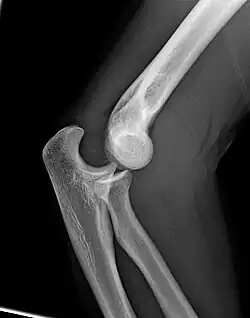

The elbow is the region between the upper arm and the forearm that surrounds the elbow joint.[1] The elbow includes prominent landmarks such as the olecranon, the cubital fossa (also called the chelidon, or the elbow pit), and the lateral and the medial epicondyles of the humerus. The elbow joint is a hinge joint between the arm and the forearm;[2] more specifically between the humerus in the upper arm and the radius and ulna in the forearm which allows the forearm and hand to be moved towards and away from the body.[3][4] The term elbow is specifically used for humans and other primates, and in other vertebrates it is not used. In those cases, forelimb plus joint is used.[1]